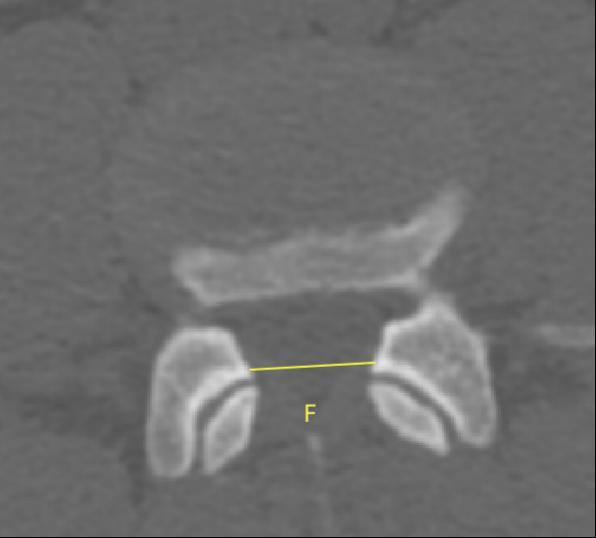

2�����、通过术前CT测量L4-5节段手术部位的(1)上位椎体后下角水平方向到关节突关节的距离(A)��;(2)纤维环后缘的中点水平方向到关节突关节的距离(B)���;(3)下位椎体后上角水平到关节突的距离(C)��;(4)上位椎体的椎弓下切迹与下位椎体椎弓上切迹连线的距离(D)���,图 6����;(5)在手术节段的棘突矢状位CT层测量椎间隙高度(E)����,图 7�����;(6)在手术节段的关节突关节横截面CT层测量关节突间距离(F)����,图 8���,再通过术中及术后CT判断患者椎间孔成型级别���,将A-F测量数据与5级成型中的各级别成型进行相关性分析����。

图 8 F的测量方式 |